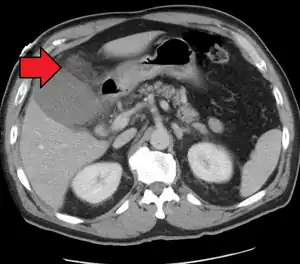

| Acute cholecystitis as seen on CT. Note the fat stranding around the enlarged gallbladder. | |

Right upper quadrant abdominal ultrasound is most commonly used to diagnose cholecystitis.[1][25][26] Ultrasound findings suggestive of acute cholecystitis include gallstones, pericholecystic fluid (fluid surrounding the gallbladder), gallbladder wall thickening (wall thickness over 3 mm),[27] dilation of the bile duct, and sonographic Murphy's sign.[13] Given its higher sensitivity, hepatic iminodiacetic acid (HIDA) scan can be used if ultrasound is not diagnostic.[13][14] CT scan may also be used if complications such as perforation or gangrene are suspected.[14]